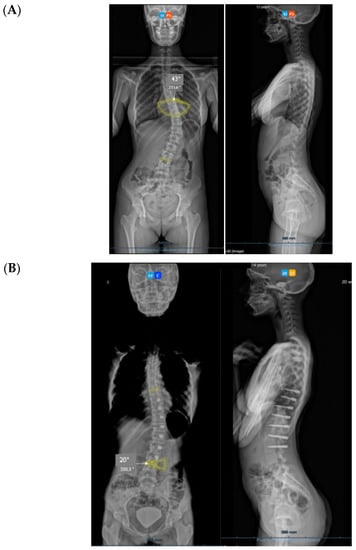

Figure 1.

(A) Thoracic scoliosis treated with Gruca Springs. (B) Double curve scoliosis treated with Gruca Springs.

From Mineiro’s archives (Figure 1), we can see that the posterior tether did work on the coronal plane for thoracic, thoracolumbar, and even double curvature scoliosis, but at that stage, orthopaedic surgeons were not concerned about the sagittal profile. Therefore, there are no lateral radiographs from these patients. In summary, looking back into the past, we can say that the posterior tether works for correcting the coronal scoliotic deformity in the adolescent growing spine (thoracic and thoracolumbar), but what would happen to the hypokyphosis of the spine in the lateral plane?